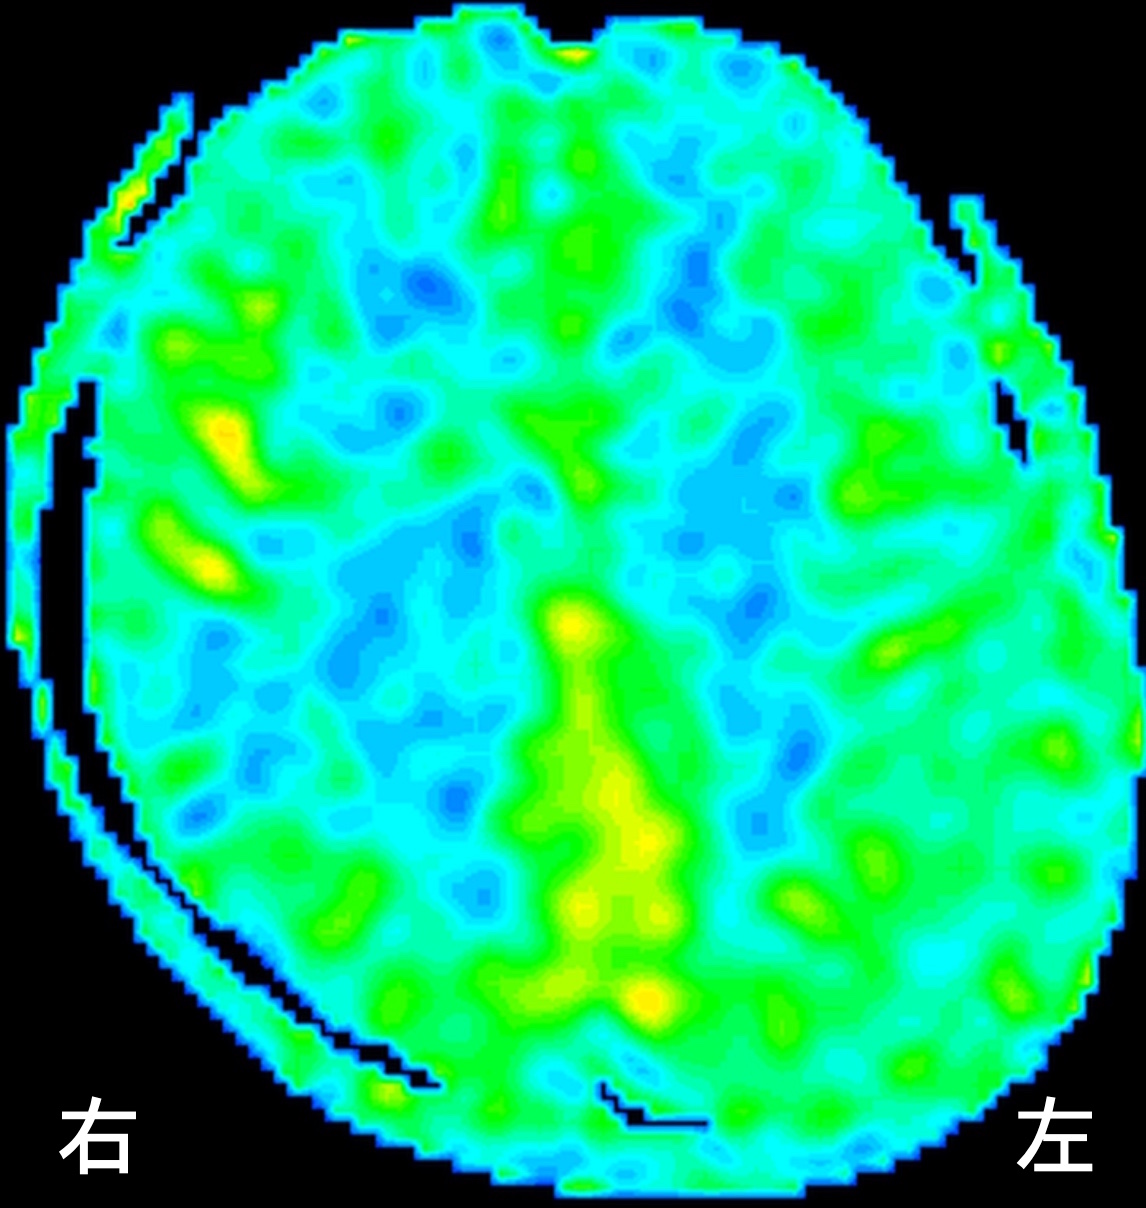

ASL後期

最初に日本で発見された「もやもや病」という病気で、厚生労働省の指定難病の一つです。このように内頚動脈という太い血管が次第に細くなり、詰まって脳梗塞を起こす事もある病気です。